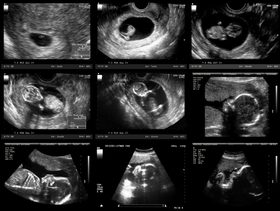

الأسبوع الثامن وأبرز النصائح والعوارض والمعلومات التي على كل حامل معرفتها في هذه المرحلة تجدينها في مجموعة من المواضيع على عائلتي